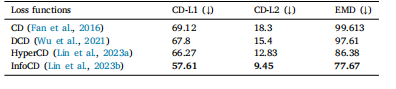

Table 4Comparison results of our model trained with some popular losses. Evaluation metricsare: 𝐶𝐷𝐿1, 𝐶𝐷𝐿2, EMD (multiplied by 1000, where lower is better.)

表4:我们的模型使用一些常见损失函数进行训练后的比较结果。评估指标包括:𝐶𝐷𝐿1、𝐶𝐷𝐿2、推土机距离(EMD,乘以1000,数值越低越好) 。